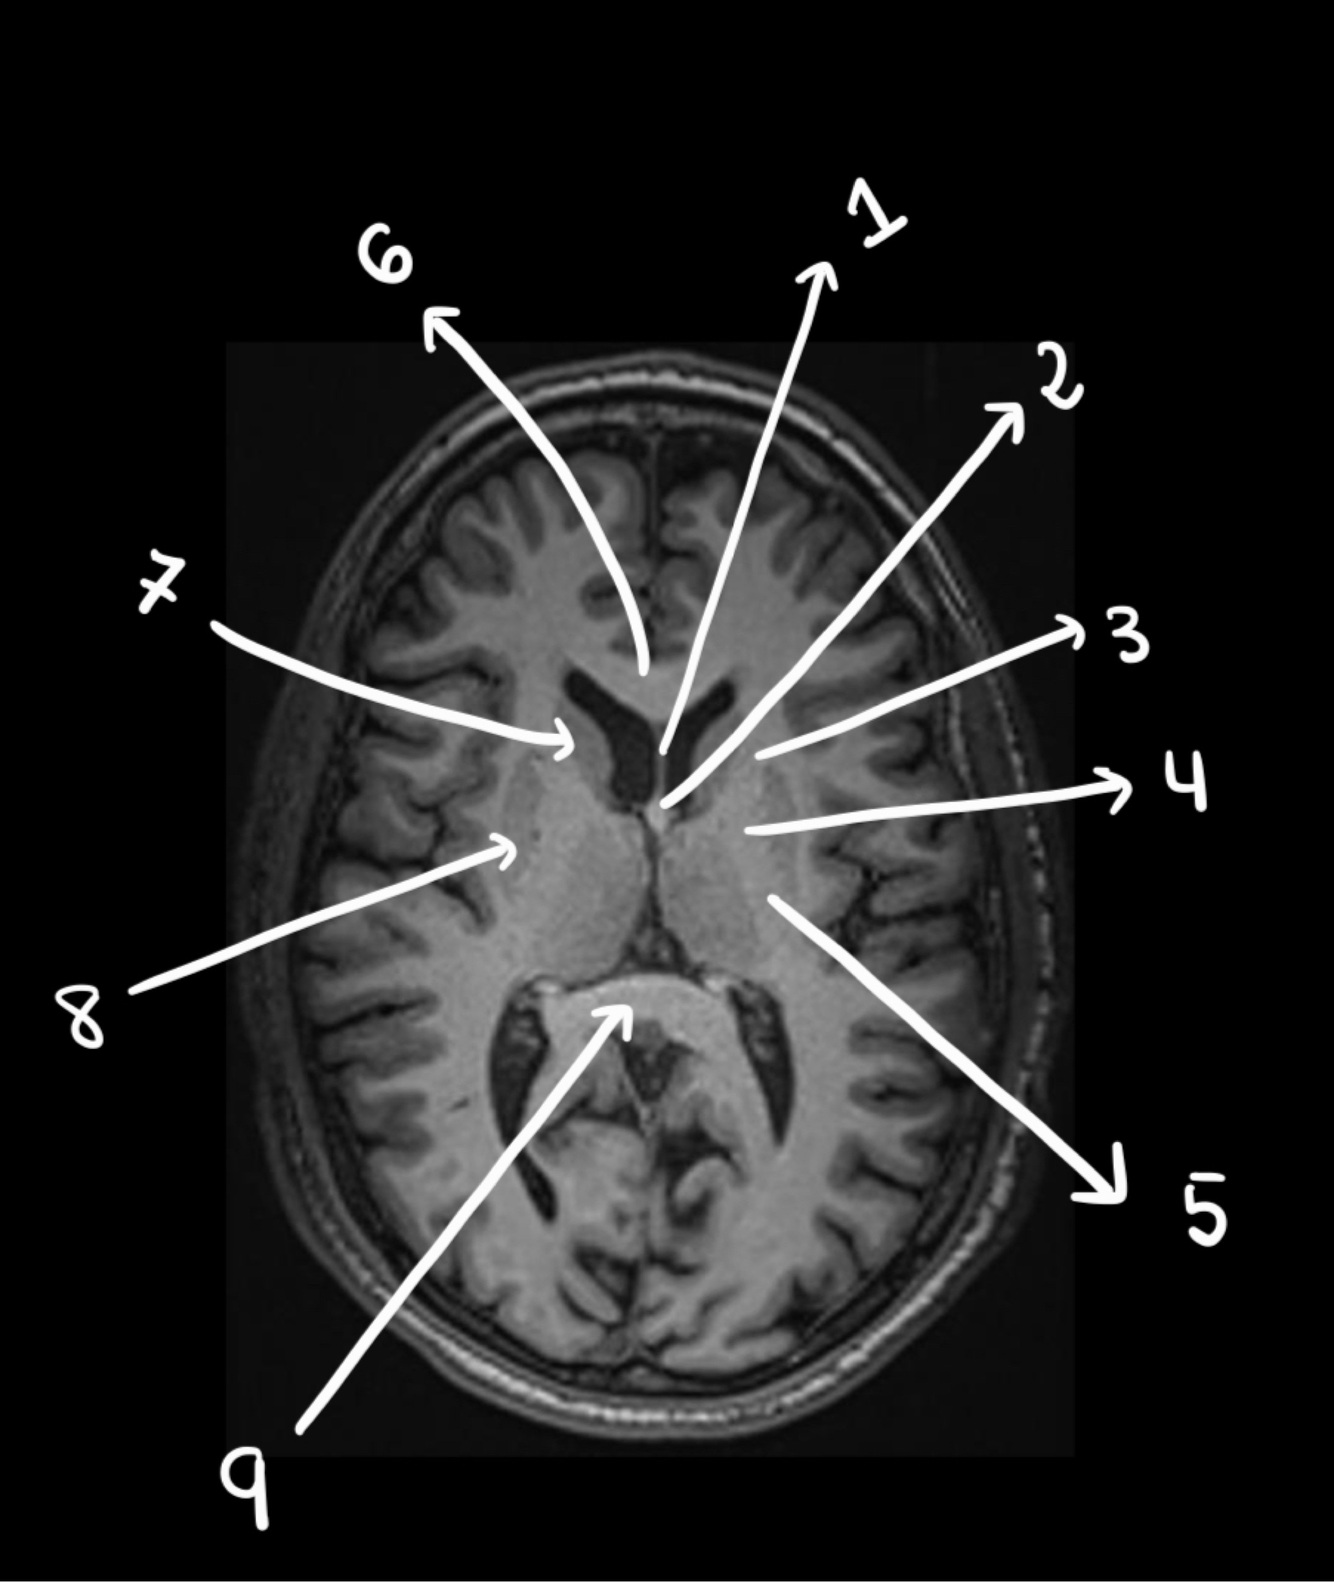

Representación esquemática HOMUNCULO MOTOR

A

11

Q

A lesion in this area might cause, problems in the contralateral… (hand/leg)

HAND (more lateral)